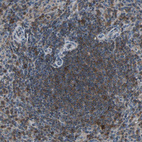

Immunohistochemical staining of human spleen shows moderate cytoplasmic positivity in cells in white pulp.